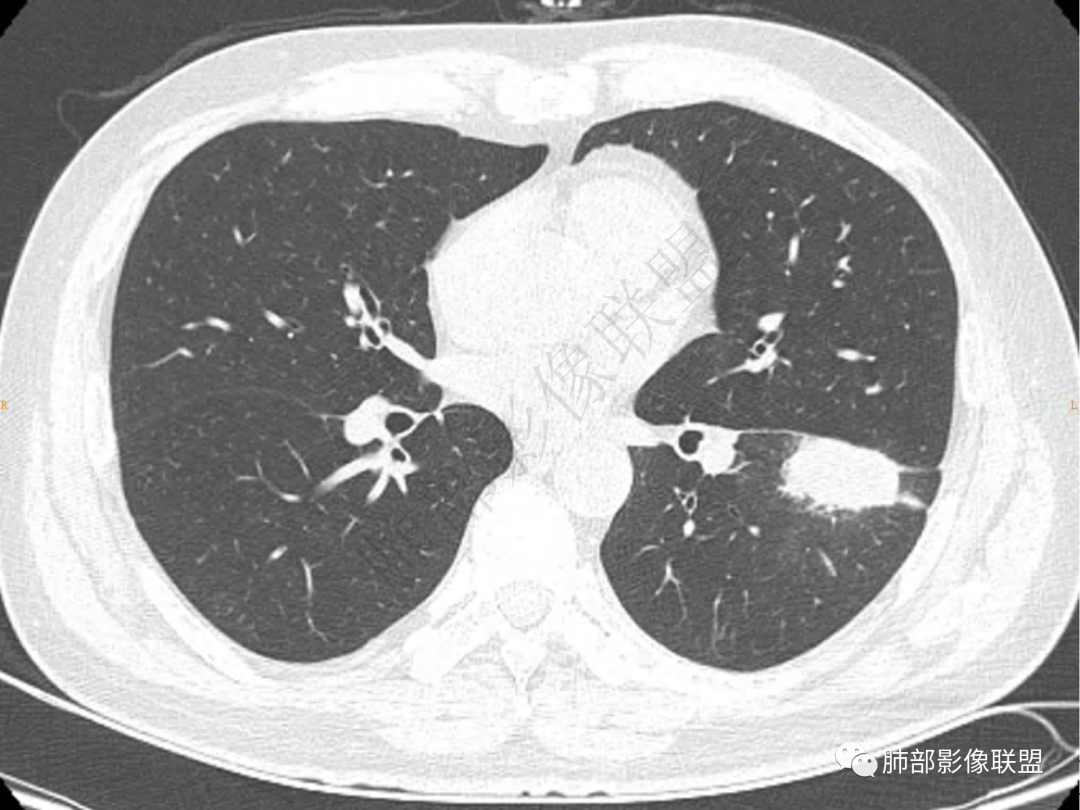

1.中年男性,咳嗽咳痰20余天,间断咯血2周

2.左肺下叶团片影,跨背段及内前基底段,实性部分类椭圆形,密度不甚均匀,可见毛刺及棘状突起,未见典型分叶及胸膜凹陷。病灶上下缘可见相应肺段支气管旁进侧出,管壁轻度增厚,未见狭窄阻塞。

3.周边较大范围磨玻璃影,边界相当模糊,小叶增厚明显。注意叶裂另一侧、左肺舌段亦可见磨玻璃影及增厚的小叶间隔。未见明确卫星病灶。

4.实性部分不均匀环形强化并显示一小范围低密度坏死区或空洞。较之肺窗,整体纵隔窗范围较小,提示病灶并不十分密实。抑或为不同时段图像。

5.双肺门及纵隔未见增大淋巴结。未见胸腔积液。